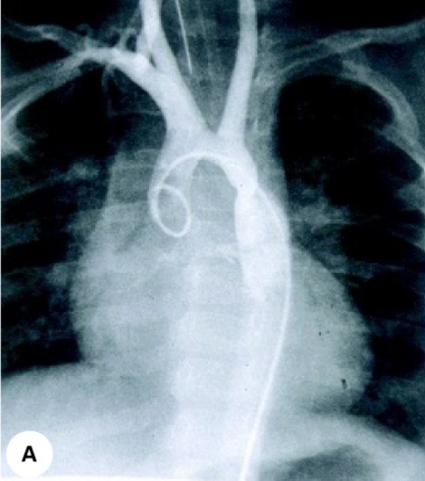

Figur 1 visar det medfödda hjärtfelet coarctatio aortae, framställt med angiokardiografi, ekokardiografi och MR.

Edgar Mannheimer, som internationellt accepterats som den europeiska barnkardiologins fader, kom tidigt i kontakt med den angiokardiografiska tekniken (»fluoroscopy«) som börjat användas i USA. I Sverige hade Johan Karnell och Gunnar Jönsson redan med angiografi framställt coarctatio aortae och öppetstående ductus, och nu fortsatte man att använda intrakardiella kontrastinjektioner för diagnostik av andra medfödda hjärtfel. En internationellt mycket framgångsrik grupp med Edgar Mannheimer, Ulf Rudhe, Sven Roland Kjellberg och Bengt Jonsson kartlade de flesta medfödda hjärtfelen med angiokardiografisk teknik, beskrev hemodynamiken och även den bakomliggande embryologin. De kunde 1955 publicera den klassiska läroboken »Diagnosis of congenital heart disease. A clinical and technical study by the Cardiologic Team of the Pediatric Clinic, Karolinska Hospital, Stockholm«. Gruppen kring Mannheimer och den barnhjärtkirurgi som utvecklades i Stockholm efter Clarence Crafoords första operation av coarctatio aortae 1944 [1] blev under 1950-talet ett internationellt centrum till vilket många kardiologer, toraxkirurger, radiologer och barnläkare kom från avlägsna länder för att få sin utbildning i diagnostik och behandling av medfödda hjärtfel.

Under hela det dynamiska 1950-talet och fram till början av 1980-talet var det hjärtkateterisering med angiokardiografi som användes för att kartlägga medfödda hjärtfel. Elektrokardiogram, fonokardiogram och slätröntgen var kompletterande metoder. Som underläkare på »Barnkardiologen« fick man snabbt stor erfarenhet av friläggningar, kateterisering av navelkärl och så småningom av den perkutana punktionstekniken, som introducerades av Sven Ivar Seldinger och som snabbt ersatte den suprasternala punktionstekniken som Stig Radner använt. Beredskap fanns hos hela kateteriseringsteamet dygnet runt. Många nyfödda barn med cyanos till följd av neonatal lungsjukdom, men utan hjärtfel, blev hjärtkateteriserade för att utesluta cyanotiska hjärtfel. Lokalbedövning och sk lytisk cocktail gav inte alltid tillfredsställande sedering, och jämfört med dagens teknik och metoder var det ibland en ganska obehaglig undersökning för de små barnen. Idag används hjärtkateterisering på barn med medfödda hjärtfel sällan i diagnostiskt syfte, men allt oftare för kateterburna kardiovaskulära interventioner, och under narkos med kvalificerad barnanestesiologisk övervakning. Den angiokardiografiska tekniken kom att helt dominera som diagnostisk metod vid medfödda hjärtfel ända fram till ultraljudets genombrott.